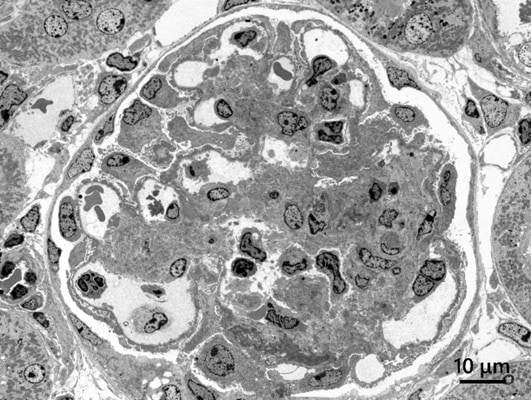

⾼衬度观察例(HC模式)

样品:大鼠肾脏

加速电压:80 kV, 观察倍率:300倍